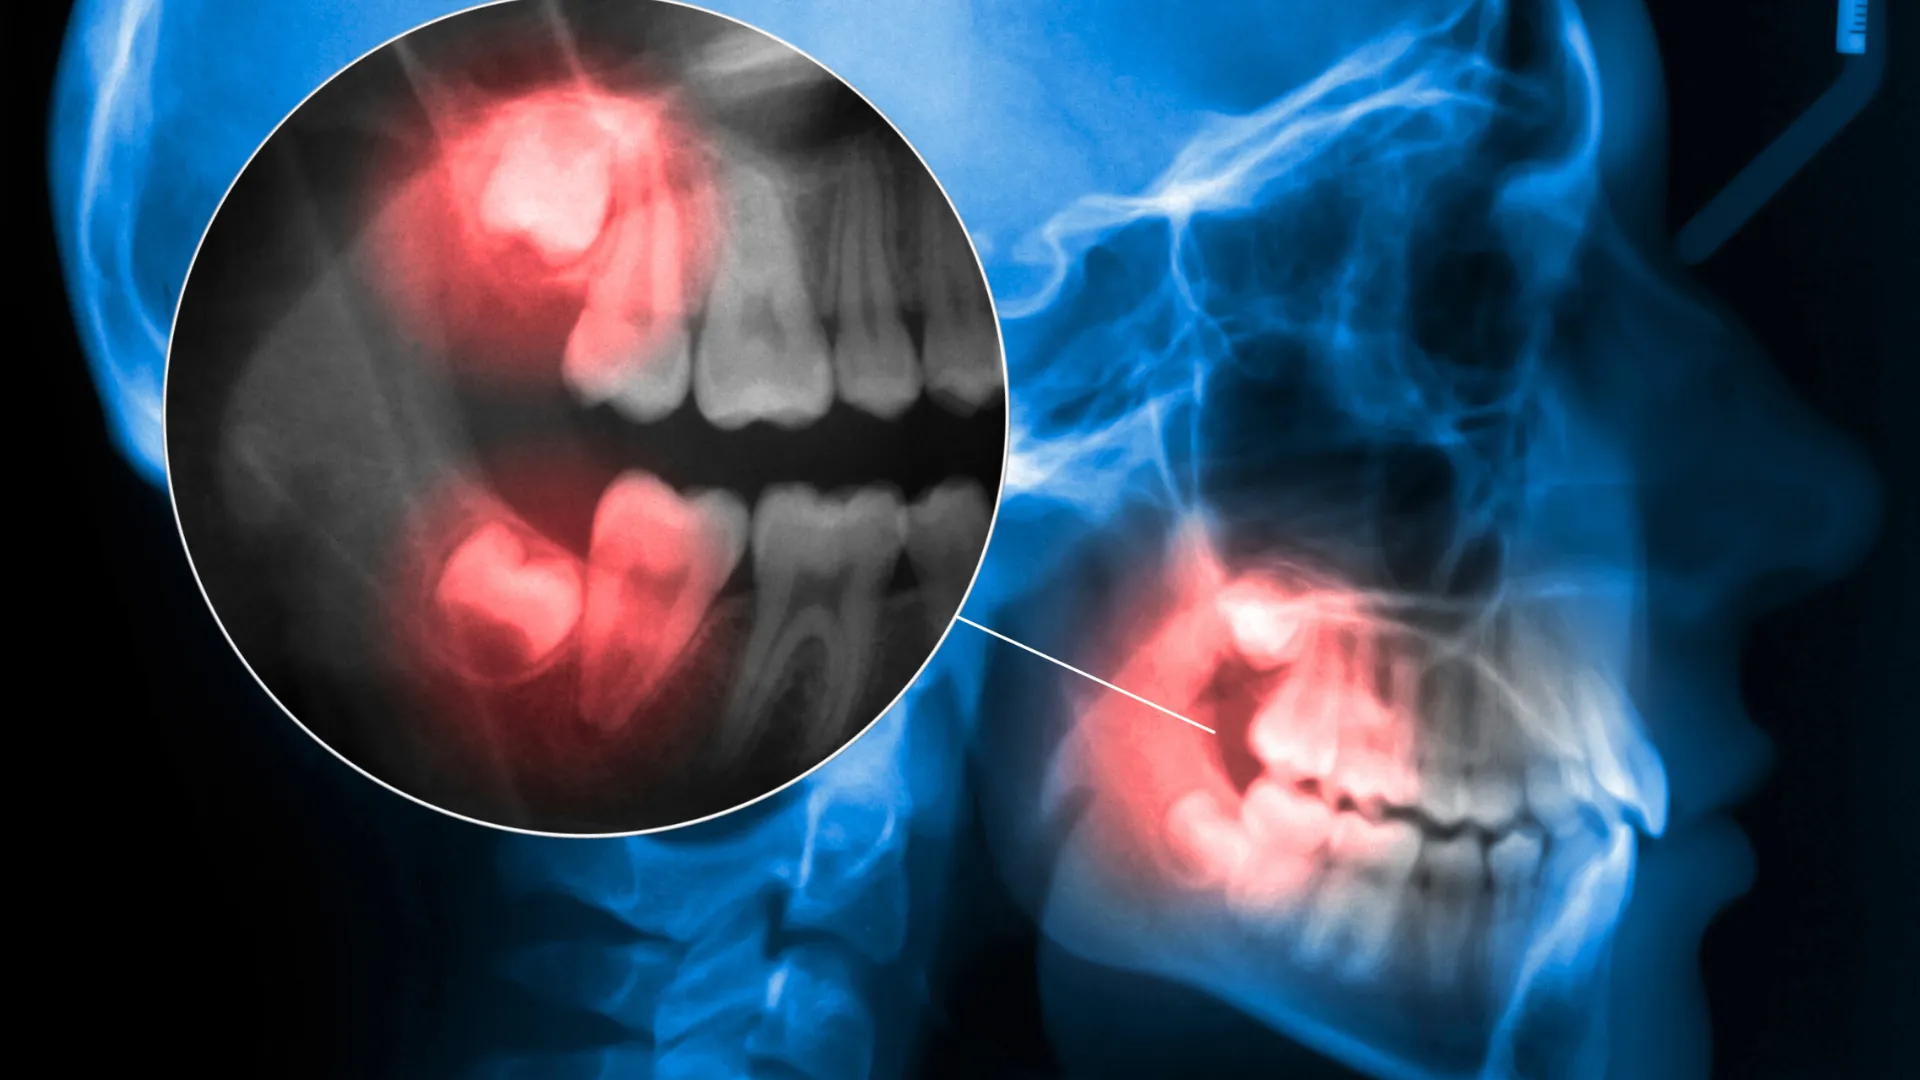

Wisdom Tooth Pain: Causes, Symptoms, and Solutions

Wisdom tooth pain is discomfort associated with the eruption or impaction of the third molars, commonly known as wisdom teeth.

These teeth typically appear between the ages of 17 and 25 and can cause a variety of issues if they don’t emerge properly.

Causes of Wisdom Tooth Pain

• Impacted Wisdom Teeth: Impacted wisdom teeth are those that don’t have enough room to emerge or develop normally. They may grow at odd angles or remain trapped within the jaw. This can lead to pain, swelling, and even damage to other teeth.

During a dental examination, your dentist will check for signs of wisdom tooth problems and may use x-rays to determine the position and condition of your wisdom teeth.